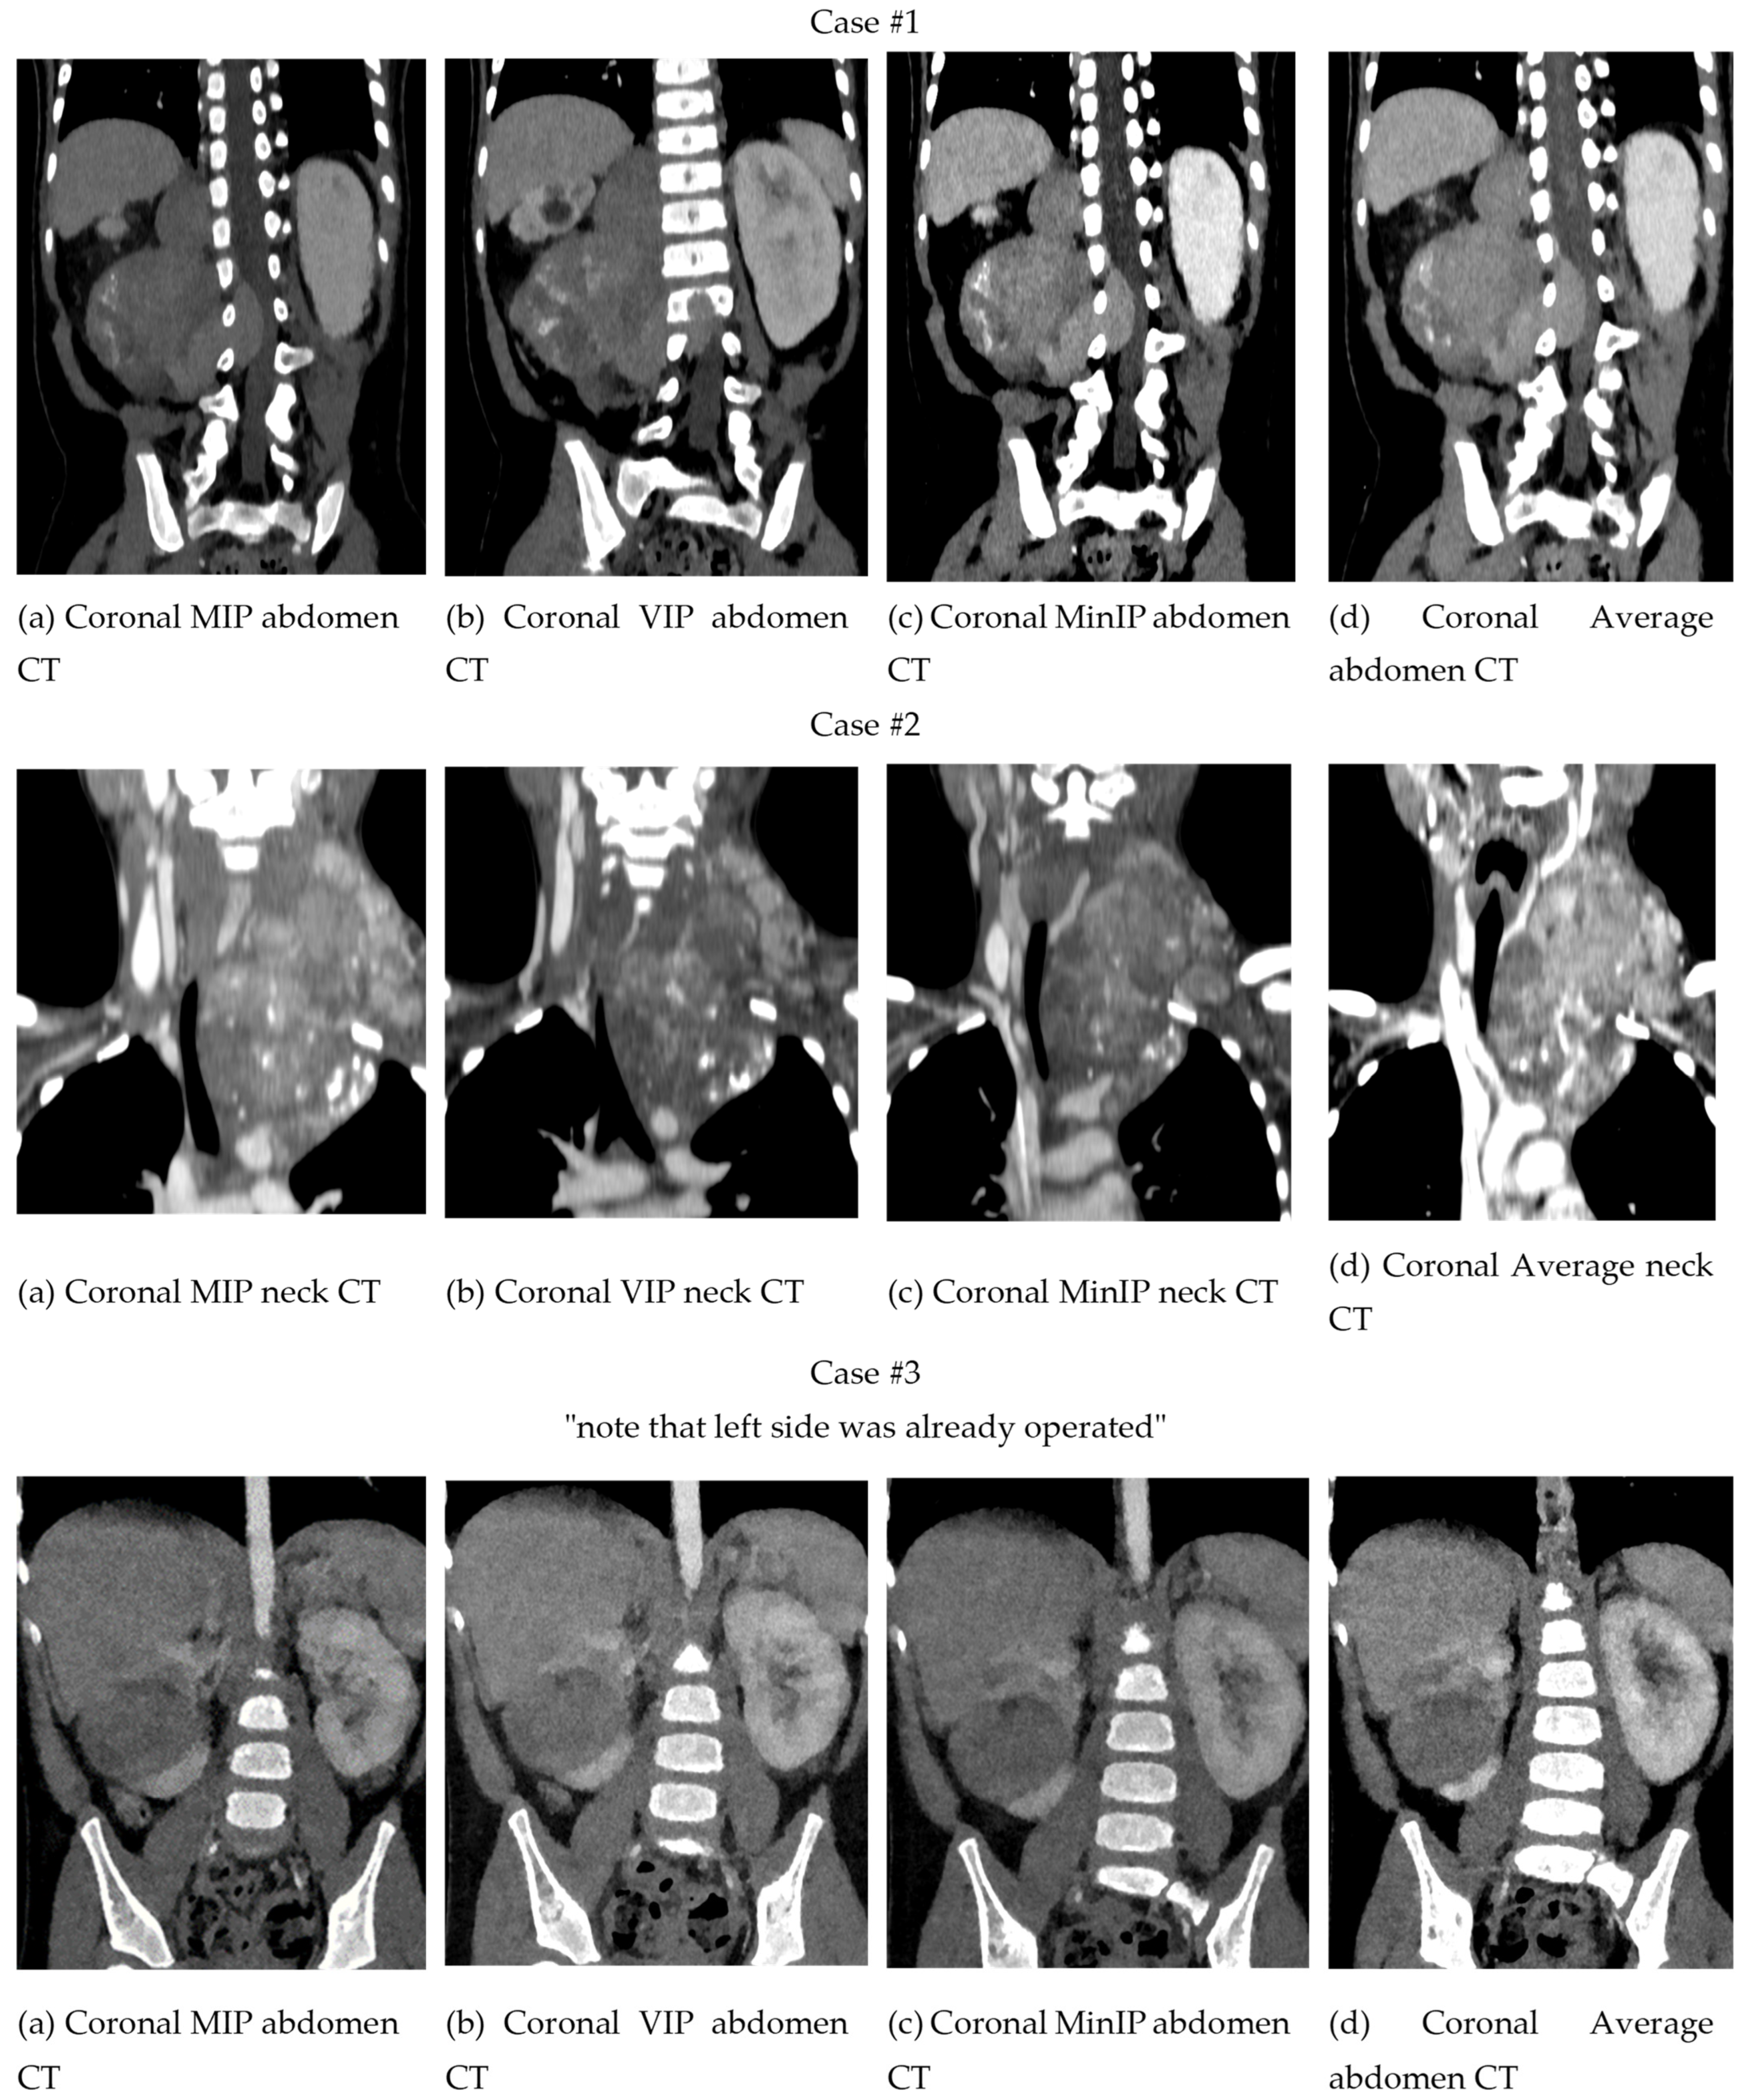

3.1.1. Two-Dimensional Projection Renderings